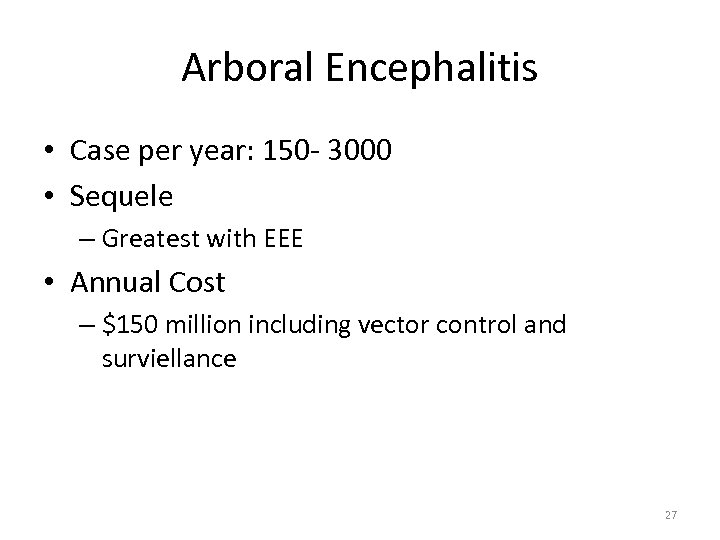

Arboral Encephalitis • Case per year: 150 - 3000 • Sequele – Greatest with EEE • Annual Cost – $150 million including vector control and surviellance 27